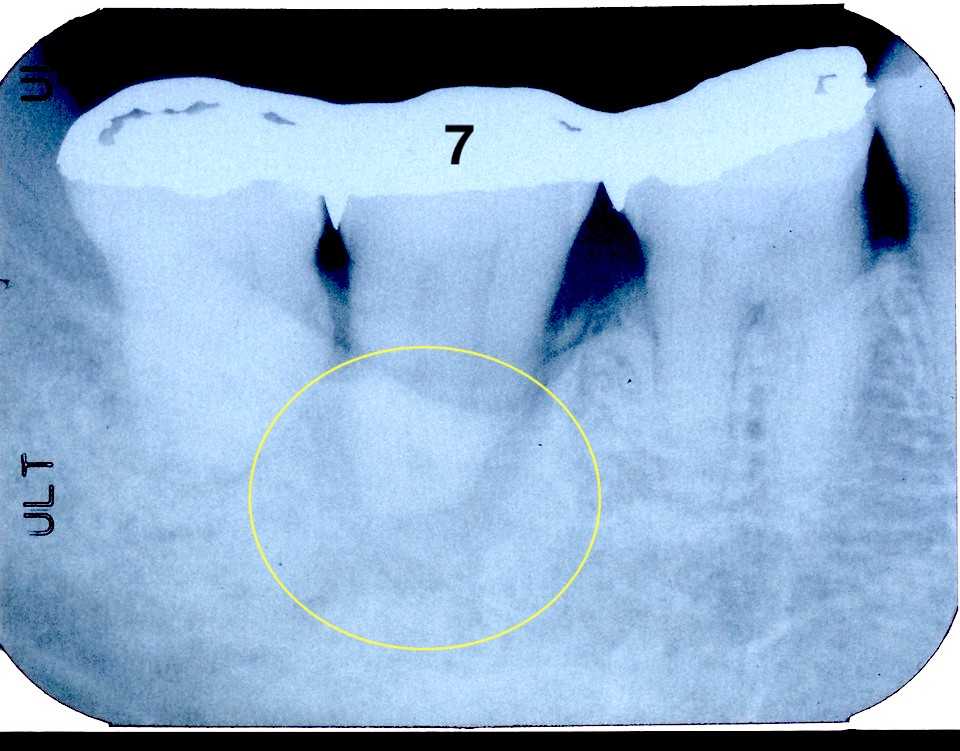

70代女性、右下7、咬合性外傷による歯髄壊死、自発痛+レントゲン写真を見ると根尖付近の陰影が強いので歯髄は壊死している可能性が高いことがわかる。このような症例は5分で終わることができて、しかも予後が極めて良い伝説の根管治療法を無料で完全公開しておきます。とりあえずインレーを除去して天蓋も除去して歯髄を見てみることにした。超音波スケーラーのエンドチップ#20 21mmで根管を洗浄。根管内の有機質を除去しようとか根管開拡しようとか、無駄どころか感染の機会を増やしてしまうことは一切必要ない。根管は水平エアブロウするだけで感染させるだけの乾燥工程は必要はない。1回目の3MIX+α-TCP精製水練りをディスポシリンジで充填し、エンドチップで押し込む。僕が使っているボンディング材はこちら。1回目のα-TCPは精製水練り。浸透性が良いが硬化が遅い3MIX+α-TCPを根管内に入れるだけで良い。緊密充填など考える必要はない。2回目はα-TCPの50%クエン酸練り(硬化する)。この上からCRダイレクトボンディングでカバーする。3MIXの作り方はこちら。α-TCPの入手法はこちら1回目2回目CRでカバーして終了。